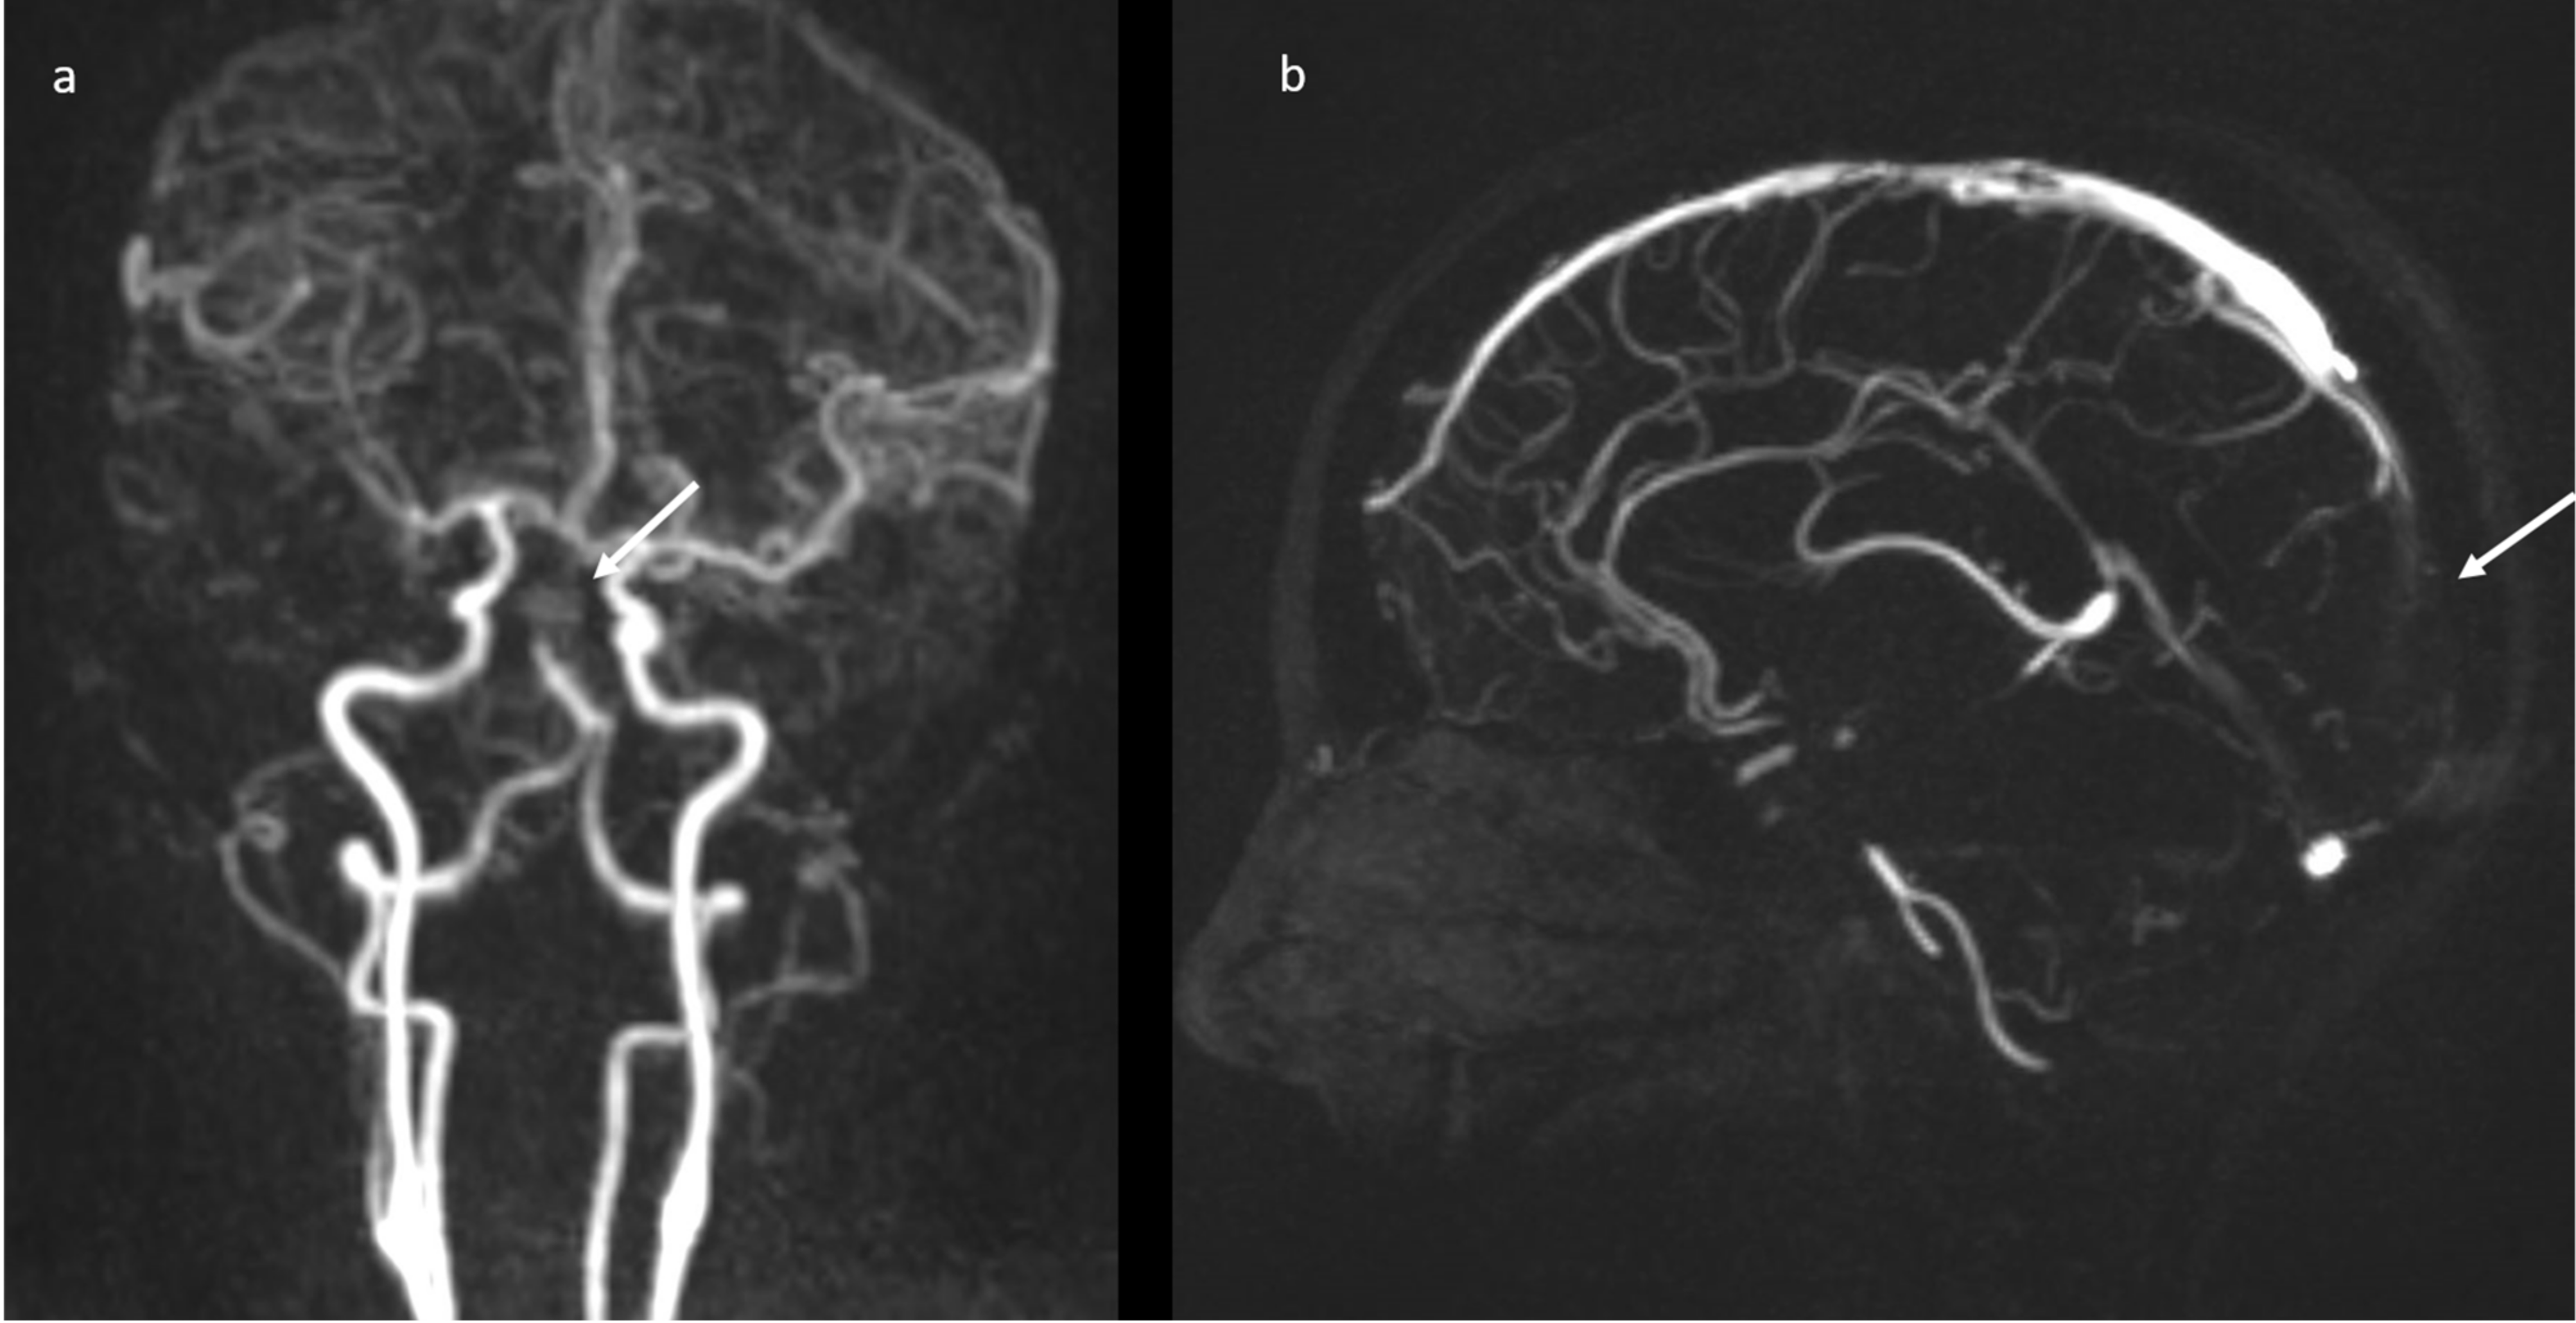

Brain magnetic resonance imaging (MRI) in the same day showed the presence of an acute basilar thrombosis (Figure 5a) associated with the superior sagittal sinus thrombosis (Figure 5b) with the delineation of hyperacute ischemic lesions in the vascular territory of the right posterior cerebral artery and of the perforating pontine branches (Figure 6).

Figure 5.

MR-angiography: acute basilar thrombosis associated with superior coronal (a) and sagittal (b) sinus thrombosis.

Figure 6.

Brain MRI (DWI): acute ischemic lesion with restricted diffusion involving the pons, mesencephalon, the right superior cerebellar hemisphere with the vermis (a), and the right posterior temporal lobe (b).